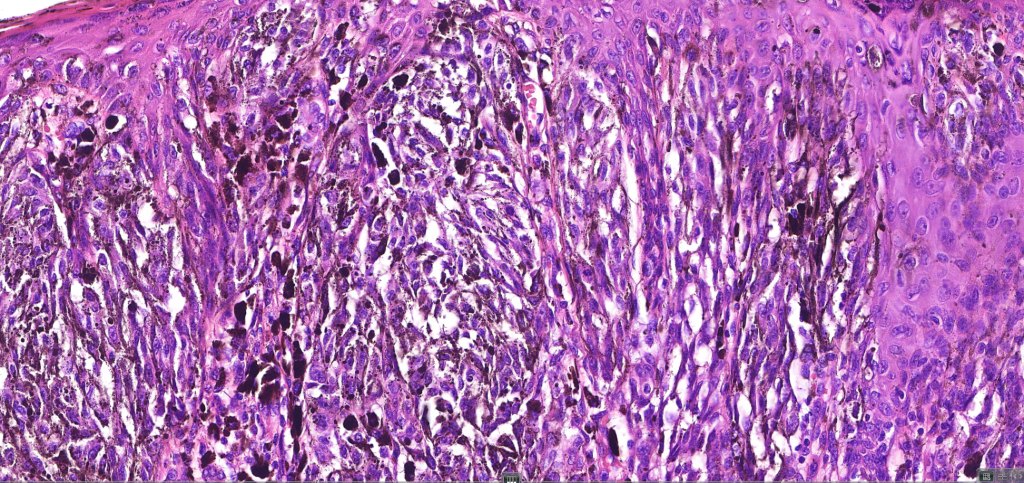

•Vertically orientated oval junctional nests

. Heavy pigmentation although hypopigmented/amelanotic varinats can be encountered

•Spindle cells with small nucleoli

•Mild pleomorphism

•Kamino bodies